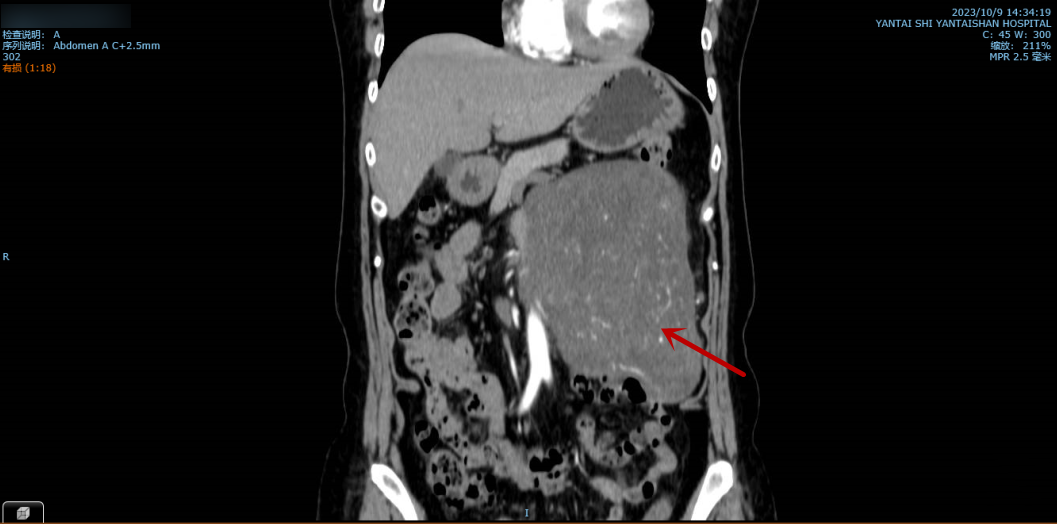

图中所示为巨大腹膜后肿瘤。

这2个月以来,孙女士的腹部日渐隆起,并出现压迫症状,腹痛、腹胀较以前更为严重,稍多进食就会呕吐。住院后的增强CT检查显示:腹膜后巨大肿瘤压迫十二指肠及空肠起始段并导致梗阻,肿瘤和腹主动脉、下腔静脉等大血管关系密切,肿瘤指标明显升高。如此以来,手术难度进一步增加,但患者的腹痛及压迫症状持续加重中,手术迫在眉睫。